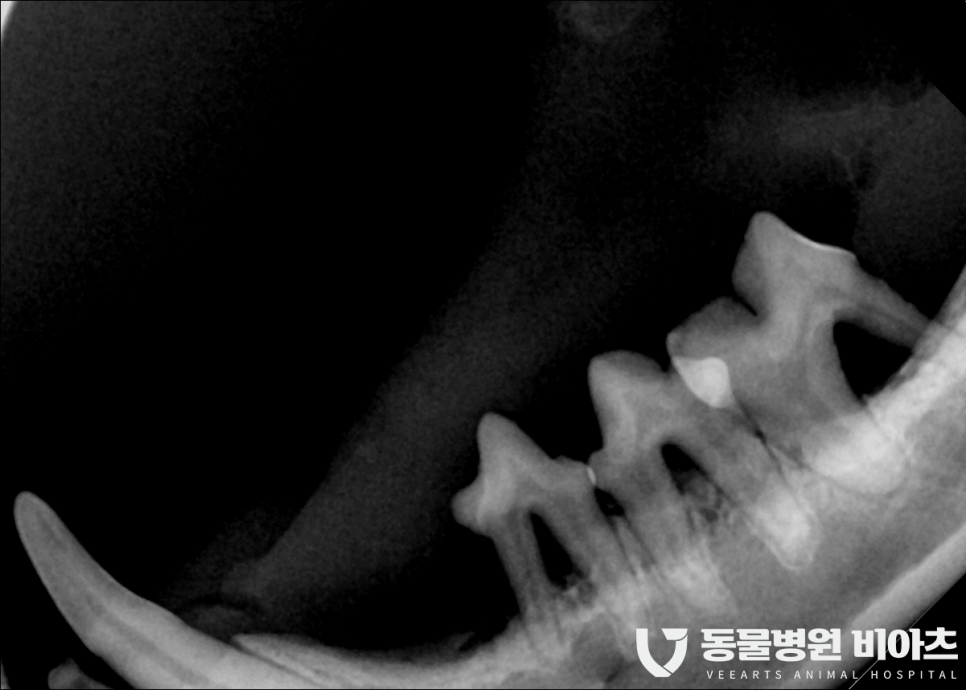

수술 전 치과 엑스레이를 통해

최소 10컷 이상의 촬영을 합니다.

치과 엑스레이는 보통 발치 전 발치 후

모두 찍습니다.

엑스레이 촬영을 통해 뿌리까지 완벽히 제거가

되었는지 확인을 해야 하기 때문입니다.

그냥 사진만 봐도

상태가..

많이 안 좋습니다..